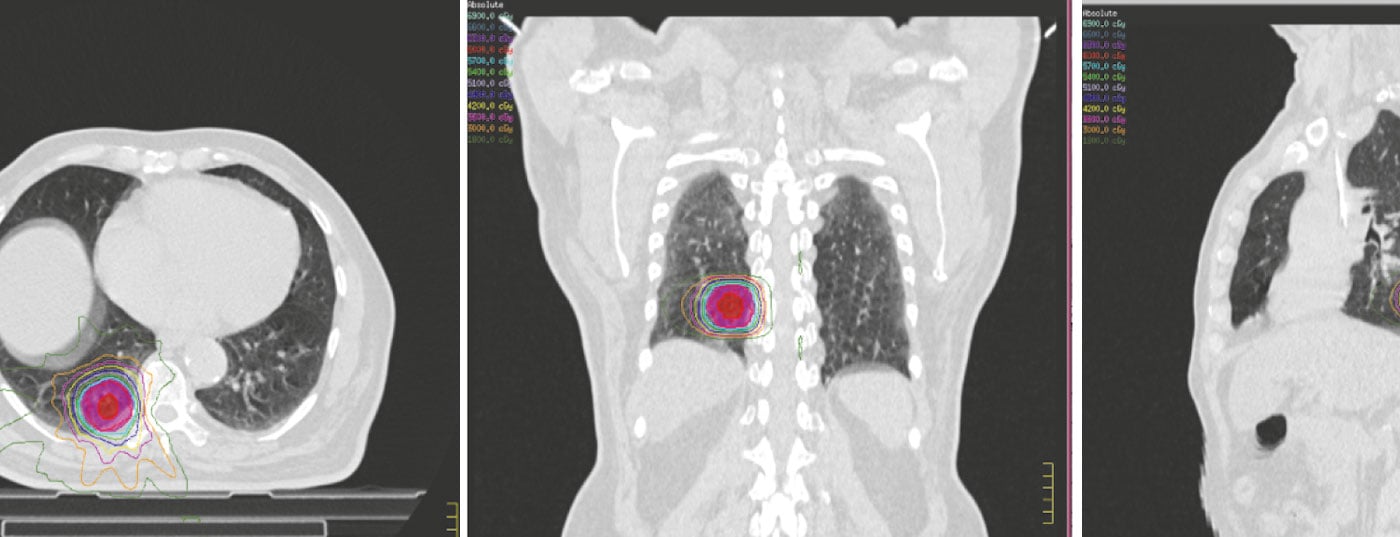

La plupart des patients font l’objet d’une évaluation détaillée dans les différents comités multidisciplinaires de lutte contre les tumeurs afin de définir l’approche thérapeutique optimale en fonction de la tumeur et des caractéristiques du patient. Une fois la radiothérapie envisagée, le patient subit une série d’étapes pour la planification de la radiothérapie visant principalement à minimiser la dose aux structures critiques tout en délivrant des doses adéquates à la tumeur et aux stations nodales adjacentes (Fig. 2).

Comme les tumeurs pulmonaires suivent les mouvements respiratoires, il est obligatoire de prendre en compte le mouvement respiratoire et les déplacements résultants de la lésion primaire dans le poumon. Plusieurs méthodes sont actuellement disponibles. Il s’agit notamment de la respiration libre ou du volume cible non interne (VCI) à l’aide d’une simulation standard de tomodensitométrie sans tomodensitométrie 4D ou fusion de scans d’inhalation ou d’expiration ; de l’approche non VCI de l’apnée ou du gating dans laquelle une seule image de tomodensitométrie 3D est acquise à un niveau de respiration prédéterminé ; de l’utilisation de compressions abdominales pendant la tomodensitométrie ; Approche CT 4D, qui implique l’acquisition d’au moins deux ensembles d’images CT 3D en fin d’inspiration ou en fin d’expiration et jusqu’à dix ensembles de données CT 3D correspondant aux différents niveaux du cycle respiratoire. Le CT 4D serait utilisé pour définir les volumes cibles tandis qu’un CT séparé à respiration libre est acquis pour la planification du traitement et les calculs de dose. Les volumes cibles résultants sont généralement définis selon les rapports 62 et 83 de l’ICRU [6,7]. Une discussion détaillée à ce sujet dépasse le cadre de cet article et les lecteurs intéressés peuvent se référer aux rapports 62 et 83 de l’ICRU pour un examen complet.

Une fois les volumes cibles et les organes à risque délimités, la planification du traitement est entreprise afin d’optimiser la combinaison de faisceaux coplanaires ou non coplanaires avec des pondérations, des angles, des formes et des temps de passage des faisceaux différents, en fonction de la technique de traitement à utiliser – 3D CRT, IMRT et VMAT. Une dose de rayonnement définie et le calendrier de fractionnement sont décrits avec des contraintes de dose spécifiées pour divers organes à risque, notamment les poumons, la moelle épinière, l’œsophage, le plexus brachial et le cœur. Les différents plans de traitement alternatifs font l’objet d’une évaluation minutieuse et le plan final est sélectionné sur la base de l’évaluation des histogrammes dose-volume pour les doses aux volumes cibles et aux différents organes à risque. L’administration du traitement se fait généralement sous une surveillance attentive et se déroule en respiration libre, en apnée ou en gating. Tous ces éléments auraient besoin d’une imagerie embarquée pour minimiser les erreurs entre les plans de traitement et leur exécution quotidienne.